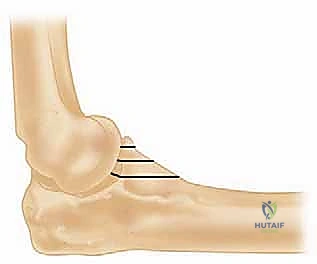

- الناتئ الإكليلي (Coronoid Process): هذا هو حجر الزاوية في إصابة الثالوث الرهيب. إنه بروز عظمي أمامي يشبه المنقار. يلعب دوراً حيوياً كمصدة ميكانيكية تمنع خلع الكوع للخلف. كما أنه يوفر نقطة ارتكاز قوية للكبسولة الأمامية والرباط الجانبي الإنسي. كسر هذا الناتئ يعني فقدان الحاجز الأمامي الأساسي، مما يجعل الكوع ينزلق للخلف بسهولة تامة.

- عظمة الكعبرة (Radius): العظم الأصغر في الساعد من الناحية الوحشية (الخارجية).

- رأس الكعبرة (Radial Head): جزء علوي مستدير يشبه القرص، يتمفصل مع رأس العضد. يُعد رأس الكعبرة "المثبت الثانوي" الأهم ضد إجهاد الإبهام (Valgus Stress) وضد عدم الاستقرار الخلفي، خاصة عندما تتمزق الأربطة الإنسية (كما يحدث في الثالوث الرهيب). إذا تم استئصال رأس الكعبرة المكسور دون استبداله في وجود تمزق في الأربطة، فإن الكوع سيصبح غير مستقر تماماً.

2. كسر في رأس الكعبرة (Radial Head Fracture): وهو الجزء الذي يتحمل العبء الأكبر من القوى الضاغطة في الكوع.

3. كسر في الناتئ الإكليلي للزند (Coronoid Process Fracture): وهو الصدادة العظمية الأمامية التي تمنع الكوع من الانزلاق للخلف.